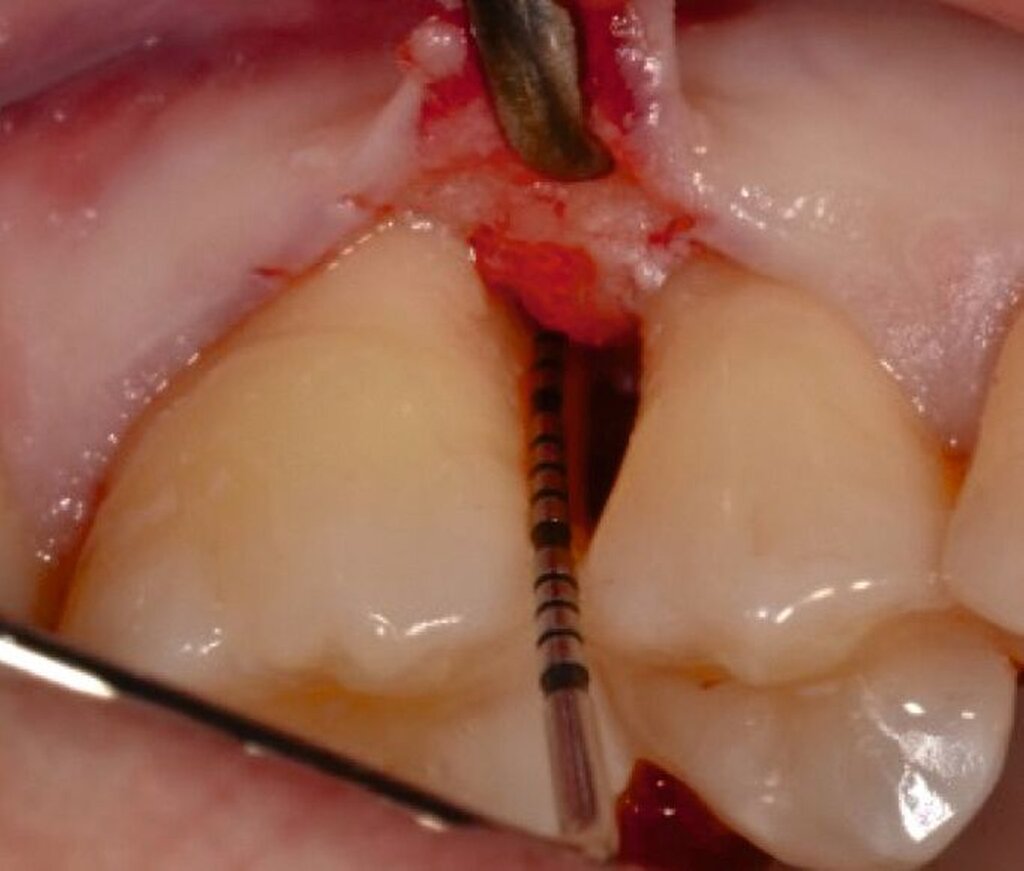

Ziel ist es, einen ausreichenden Zugang zum Defekt für eine sorgfältige Instrumentierung und die Applikation des Biomaterials zu erhalten. Bei isolierten Defekten können vertikale Entlastungsinzisionen verwendet werden. Alternativ kann der Lappen nach lateral zu den benachbarten Zähnen erweitert werden. Keratinisiertes Gewebe sollte durch intrasulkuläre Inzision und die Anhebung eines Mukoperiostlappens erhalten werden. Das Granulationsgewebe wird entfernt und die freiliegenden Wurzeloberflächen werden sorgfältig mit Handinstrumenten, oszillierenden Scalern (optional mit fein diamantierten Spitzen) oder rotierenden Instrumenten gereinigt. Wurzelanomalien wie Schmelzvorsprünge/-perlen sollten entfernt werden. Wenn EMD Teil der Regenerationsstrategie ist, wird es in der Regel nach einer zweiminütigen Wurzelkonditionierung mit Ethylendiamintetraacetat (EDTA) und Spülung mit steriler Kochsalzlösung angewendet. Anschließend kann ein Knochentransplantat/-ersatzmaterial verwendet werden, um den Furkationsdefekt aufzufüllen.

Fall 2 – fortgeschritten